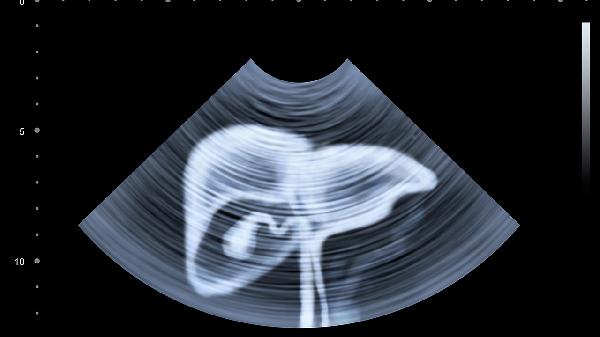

胆囊结石阻塞胆管引发炎症。右上腹疼痛在深呼吸或按压时加剧,向右肩放射。常见诱因包括高脂饮食,可能伴有发热、黄疸。超声检查可见胆囊壁增厚或结石影。